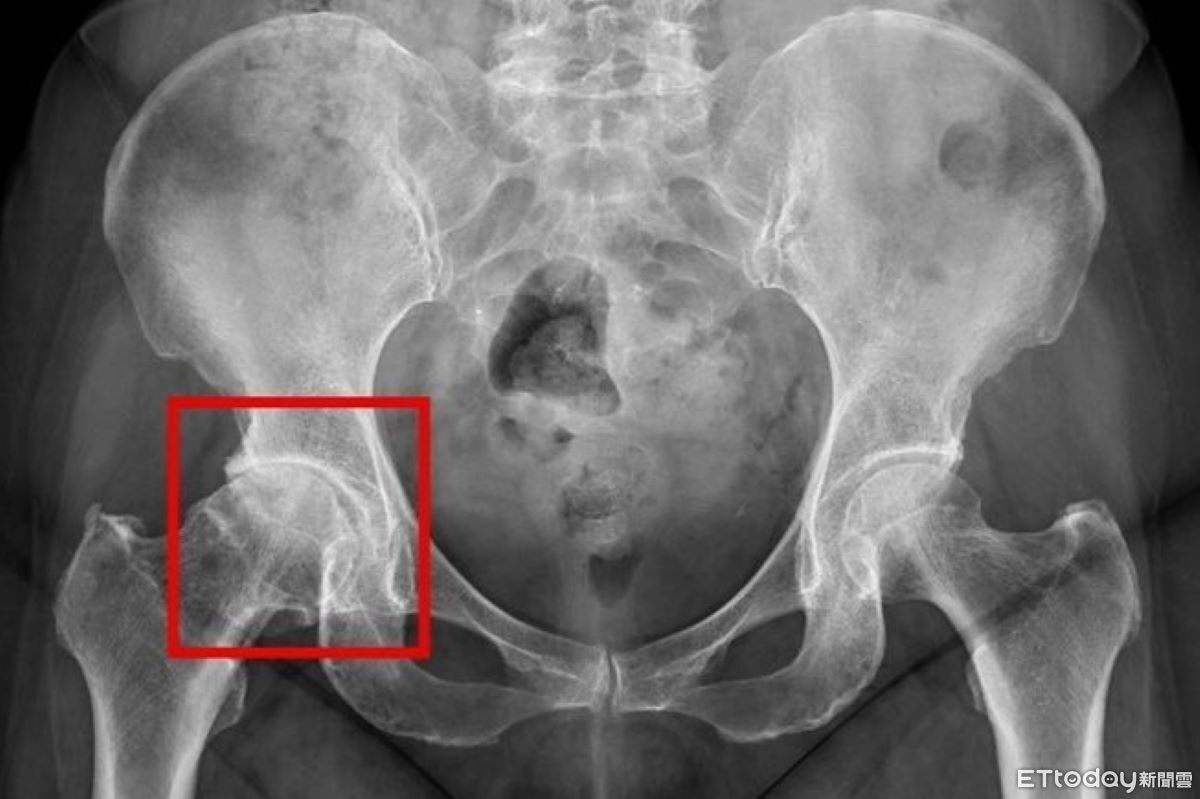

翁下背痛拖到走不動 竟是「髖關節退化」軟骨全磨光

標題: 翁下背痛拖到走不動 竟是「髖關節退化」軟骨全磨光

髖關節

軟骨

退化

下背痛